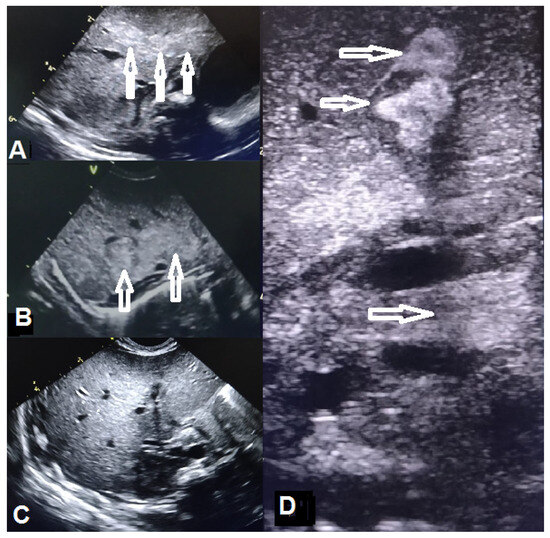

| Thoraco-abdominal radiography | No lung or abdominal involvement | Suggestive of respiratory distress syndrome due to surfactant deficiency on DOL 0; pronounced reticular, micronodular bilateral lung interstitium on DOL 5 | |||||||||||

| Abdominal ultrasound | Abdominal situs inversus on DOL 2; no abdominal parenchymal involvement on DOL 2 and 10 | Gross, inhomogenous, patchy echogenic areas disseminated, almost throughout the entire liver on DOL 9; fine granular echogenic areas limited to the fourth hepatic segment by DOL6 14; normal hepatic ultrasound structure on DOL 45 | |||||||||||